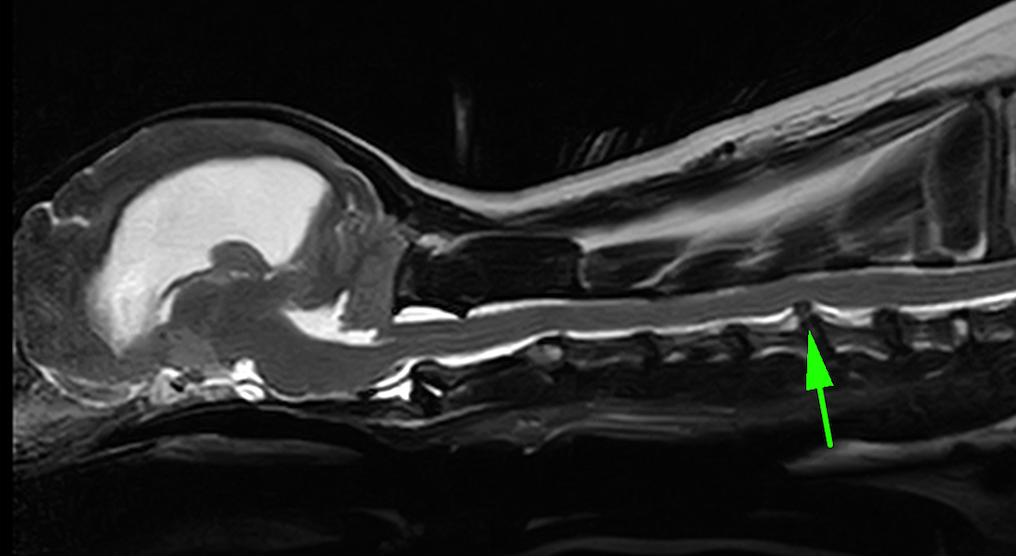

頚部椎間板ヘルニアは頚椎という首の骨をつなぐ椎間板物質が背側に飛び出してしまうことで、そこの神経を圧迫し、疼痛や麻痺を引き起こす疾患です。診断は触診や神経学的検査、レントゲン検査に加え、MRI検査が必須となります。

矢印の部分の椎間板物質が飛び出しているのがわかります。診断名は第5−6頚部椎間板ヘルニアです。

術後のフォローアップMRIです。術前のMRIで突出していた椎間板物質は取り除かれ、平滑になっているのがわかります。

術後の経過は順調で、首の痛みもなくなり生活できるようになりました。